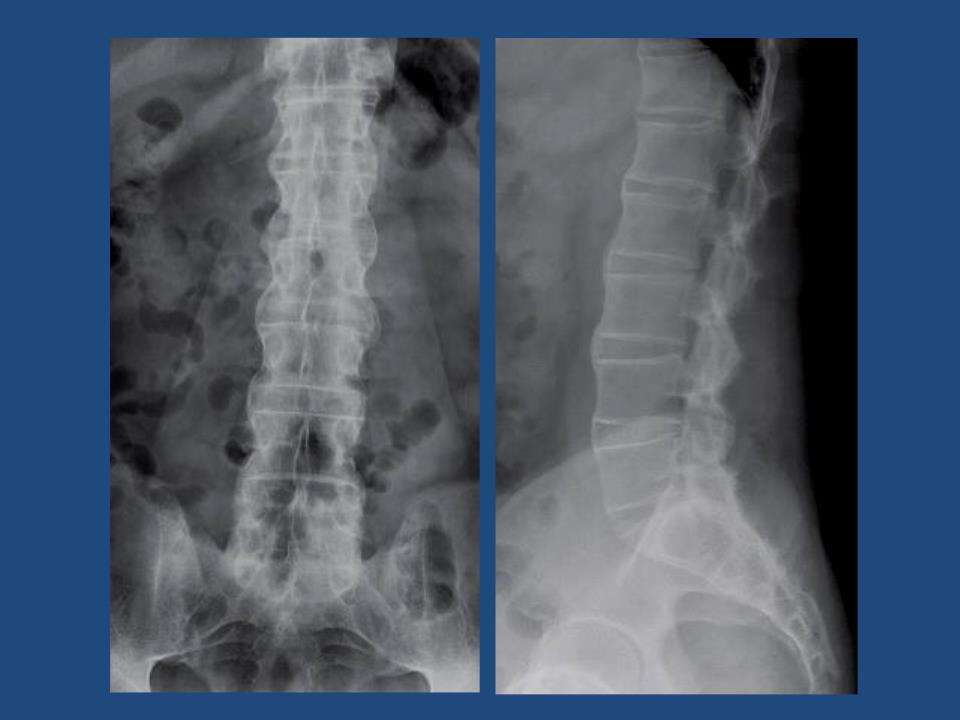

儿童强直性脊柱炎怎么治疗?脊柱炎是常见的一种疾病,其发病率有逐年增加的趋势。有不少的患者得了脊柱炎后常因为情面等原因,自己一个人默默忍受,饱受心理和生理双重压力的折磨。不仅影响治疗还加重了病情,苦不堪言。脊柱炎好不好治?其实脊柱炎这种病是可以治疗的,对于它的治疗方法目前有很多,下面介绍一下关于脊柱炎的治疗。

直性脊柱炎是一种缓慢、带有遗传倾向的疾病:教育患者澄清本病的发作、开展规律;协作医师治疗、检查,建立长明与疾病作斗争的决计;一起,还要得到患者家族、亲友和社会的多方支持,敦促患者坚持服药,坚持操练,对控制病情很有必要;患者要按医嘱守时服药,并守时去医院复查化验,了解疾病的开展以及时调整治疗。

操练与休憩:强直性脊柱炎的急性发作,会导致一些脏器出现衰竭的情况,这个时候,需要患者多进行休息,另外在绝大多数情况下,脊柱炎患者需加强腰部关节的功用操练。患者必须坚持腰部运动健身操,包括折腰、侧腰、后仰等腰部操练,平仰卧位时抬腿、提臀、挺腰、挺胸、抬颈操练和俯卧位的过伸运动操练,并常常做深呼吸及加强颈部操练,防止胸椎、颈椎破坏性固定变形。强直性脊柱炎吃什么好